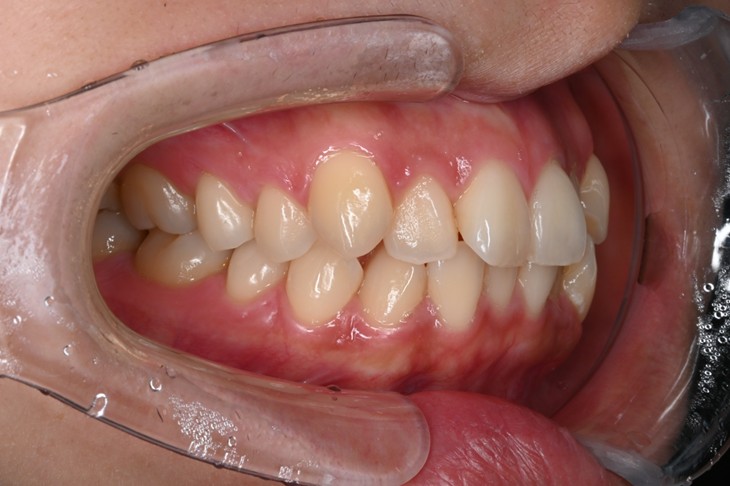

症例2:八重歯が気になる

| 患者様データ | 20代 女性 |

| 来院主訴 | 八重歯が気になる。 |

| 治療内容 | 八重歯を治すために上の親知らずを抜歯し、インビザラインにてマウスピース矯正を開始しました。かみ合わせを整えるためにゴムかけを行いました。 |

| 概算治療費 | 約85万円 |

| 治療期間 | 1年3ヶ月 |

| 通院回数 | 8回 |